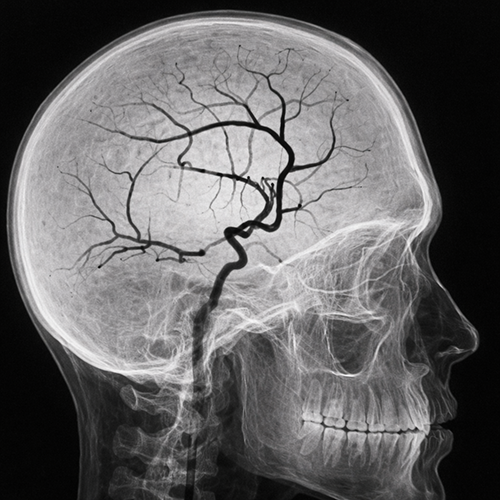

CathTrainVR is an advanced simulation platform designed to train clinicians in catheter-based interventions using immersive virtual environments. It replicates real-world angiography skills, vascular anatomy, device handling, and procedural challenges.

• Realistic, workflow-based interventional training

• Enhanced patient safety and complication management skills